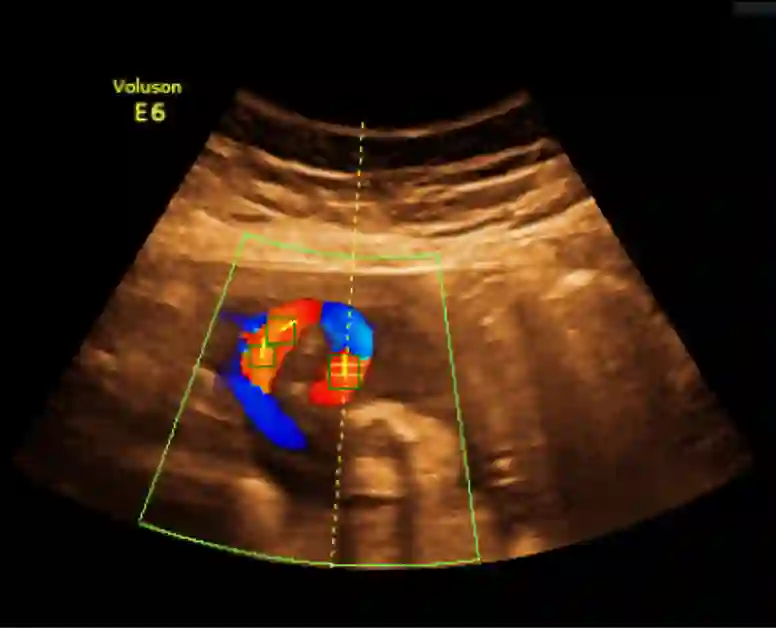

Examination of the umbilical artery with Doppler ultrasonography is performed to investigate blood supply to the fetus through the umbilical cord, which is vital for the monitoring of fetal health. Such examination involves several steps that must be performed correctly: identifying suitable sites on the umbilical artery for the measurement, acquiring the blood flow curve in the form of a Doppler spectrum, and ensuring compliance to a set of quality standards. These steps rely heavily on the operator's skill, and the shortage of experienced sonographers has thus created a demand for machine assistance. In this work, we propose an automatic system to fill the gap. By using a modified Faster R-CNN network, we obtain an algorithm that can suggest locations suitable for Doppler measurement. Meanwhile, we have also developed a method for assessment of the Doppler spectrum's quality. The proposed system is validated on 657 images from a national ultrasound screening database, with results demonstrating its potential as a guidance system.